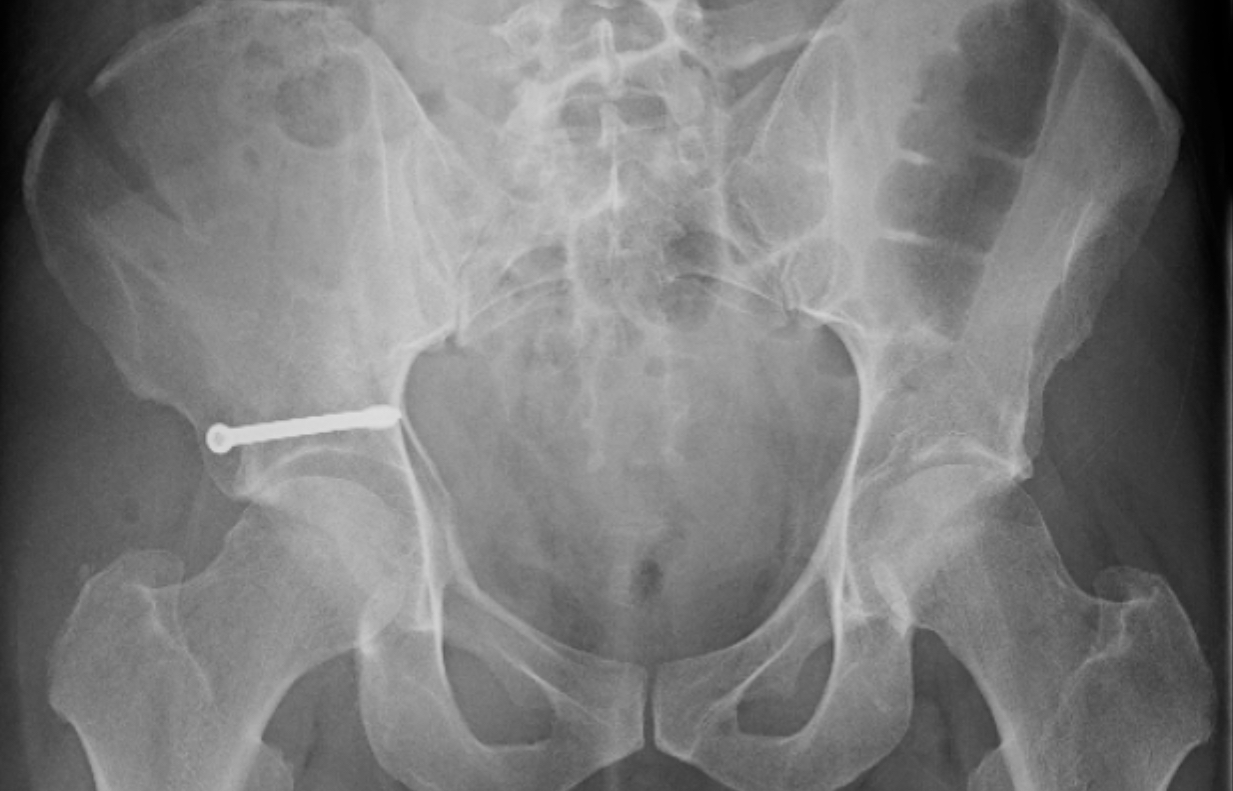

Surgery happened the afternoon of Christmas Eve. I now have a stainless steel screw in my hip, very close to the socket.

The hardware